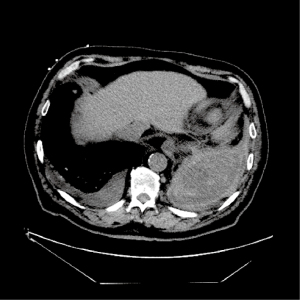

Diagnosis

Early recognition and treatment of hemothorax can be lifesaving in patients with a hemothorax. Hemothorax should be considered in all patients with thoracic trauma. TUS is a quick, inexpensive, and sensitive screening tool for the detection of hemothorax during an initial trauma evaluation. Multiple studies have shown that TUS has a higher sensitivity than chest X-ray in detecting hemothorax in patients with blunt trauma (Figure 4) (60,61). Contrast-enhanced chest CT should be performed after the initial screening to identify the source of bleeding, which may also reveal an underlying etiology and the presence of injuries to vital organs (Figure 5) (62).